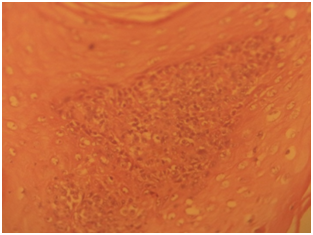

Gross specimen showed a rubbery grayish white tissue that was partly covered by an ellipse of skin and it measured 4.5x2x2 cm. The cut surface appeared solid grayish white. Histological sections showed skin tissue displaying monomorphic lymphoid cells focally arranged in a nodular pattern invading the dermis with numerous foci of epidermal infiltrations (Figure 3) (Figure 4). The cells are predominantly small and medium sizes with an occasional blast and they have round to oval vesicular nuclei that have a cerebroid configuration. Focal pautriers microabscesses and areas of necrosis are present. The feature is consistent with Mycosis fungoides.

Figure 3 Photomicrograph shows monomorphic lymphoid cells infiltrating the dermis, akin to exocytosis, H and E X100.